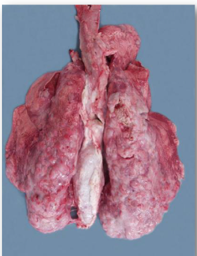

Ovine Pulmonary Adenocarcinoma (OPA)

18

Q

A

19

OPA

* Virus that causes lung tumours. Typically seen in adult ewes.

* Causes hard white areas, sometimes large consolidated regions, sometimes speckled

* Affects any part of the lungs

* There is usually much white froth in the airways